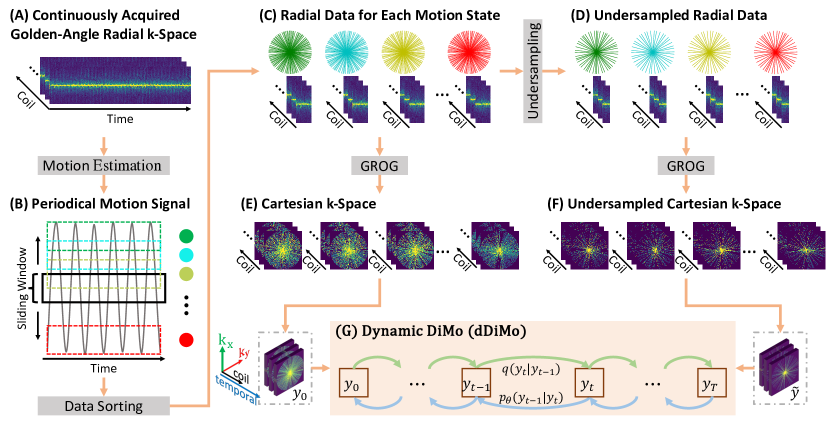

2.3 Non-Cartesian Reconstruction

While Figure 1 illustrates the schematic diagram of dDiMo for reconstructing dynamic Caterisan k-space data, this proposed method can inherently be applied to non-Caterisian reconstruction as well. In this study, we demonstrate how dDiMo was adapted to reconstruct radial data acquired using a continuous stack-of-stars golden-angle radial acquisition scheme [53]. The updated framework consists of not only the diffusion modeling of dDiMo but also a few important preparation steps to adapt dDiMo with the non-Catesion k-space trajectory, as shown in Fig. 3. We implemented a k-space binning, sorting, and data augmentation strategy to fully leverage the unique feature of this acquisition scheme for diffusion modeling. More specifically, in the data binning step, the motion signal was first estimated using a modified projection-based approach [52, 54] for the continuously acquired golden-angle radial k-space. The periodical motion signal was then divided into different motion states, and the data can be binned for each motion state. Instead of binning the data into a fixed number of non-overlapped bins, we implemented a flexible binning approach, where a sliding window with a specific number of radial spokes can be used to bin at any motion state the continuously acquired data, allowing overlapped bins to capture the smooth transition between each motion state. This flexible binning approach behaves as a data augmentation when preparing the training data pairs for diffusion model training, with two advantages, first, it can generate extensive paired data to better utilize the continuous acquisition, and second, due to the bin overlap, it allows the network to see and then learn continuous motion state between the adjacent and overlapped bins, providing better generalizability than fixed binning at fixed motion state.

After the binning using the sliding window, radial data within each bin can be sorted into the k-space to form reference training data for this specific motion state. Inspired by our previous work using sampling augmentation to improve learning performance [20], the undersampled k-space data for each motion state were generated by randomly selecting a subset of radial spokes within each reference motion bin at each training iteration. This random sampling augmentation further diversifies the training data pairs, enabling the network to capture the complete features and patterns characteristic of radial data. The non-Cartesian radial k-space for reference and undersampled data was then mapped onto a Cartesian grid using GRAPPA operator gridding (GROG) [55]. We adopt self-calibrating GROG [56, 57] to shift radial data points to their nearest Cartesian grid locations, eliminating the need for separate calibration datasets. Reformatting the data into a Cartesian grid facilitates the efficient generation of binary Cartesian masks within the dDiMo framework, as shown in Figure 1, which can be directly used for reconstructing non-Caterisian radial data, as shown in Figure 3(G).